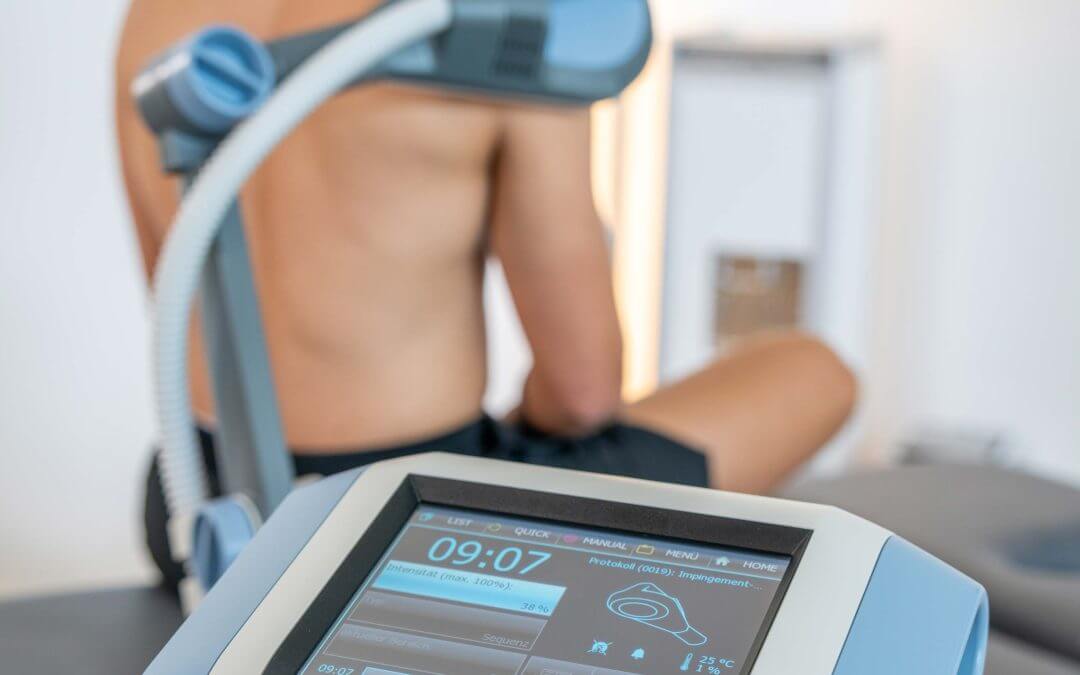

Hervorzuheben sind in der Praxis Niedergassel, die bereits seit fast 10 Jahren besteht, die modernsten Schmerztherapien, wie zum Beispiel die fokussierte Magnetfeldtherapie.

Dabei handelt es sich um das derzeit effektivste und innovativste Therapiesystem zur Behandlung von Gelenk- und Muskelschmerzen. Ein hochintensives Magnetfeld wird berührungslos auf die schmerzen- de Stelle appliziert.

Dieses intensiv zu spürende Magnetfeld hat einen schmerzlindernden und regenerierenden Effekt auf die Muskeln und Gelenke.